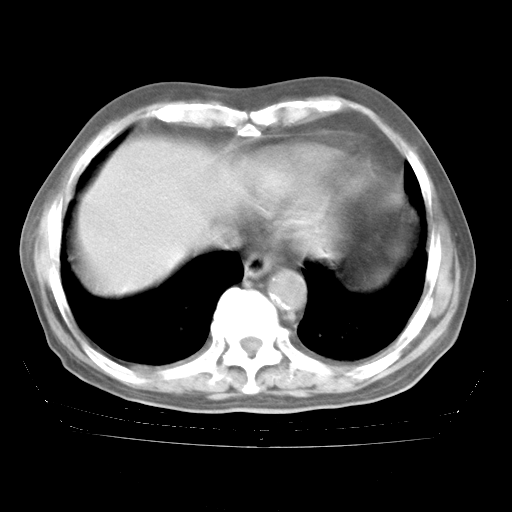

4月28日肺部CT